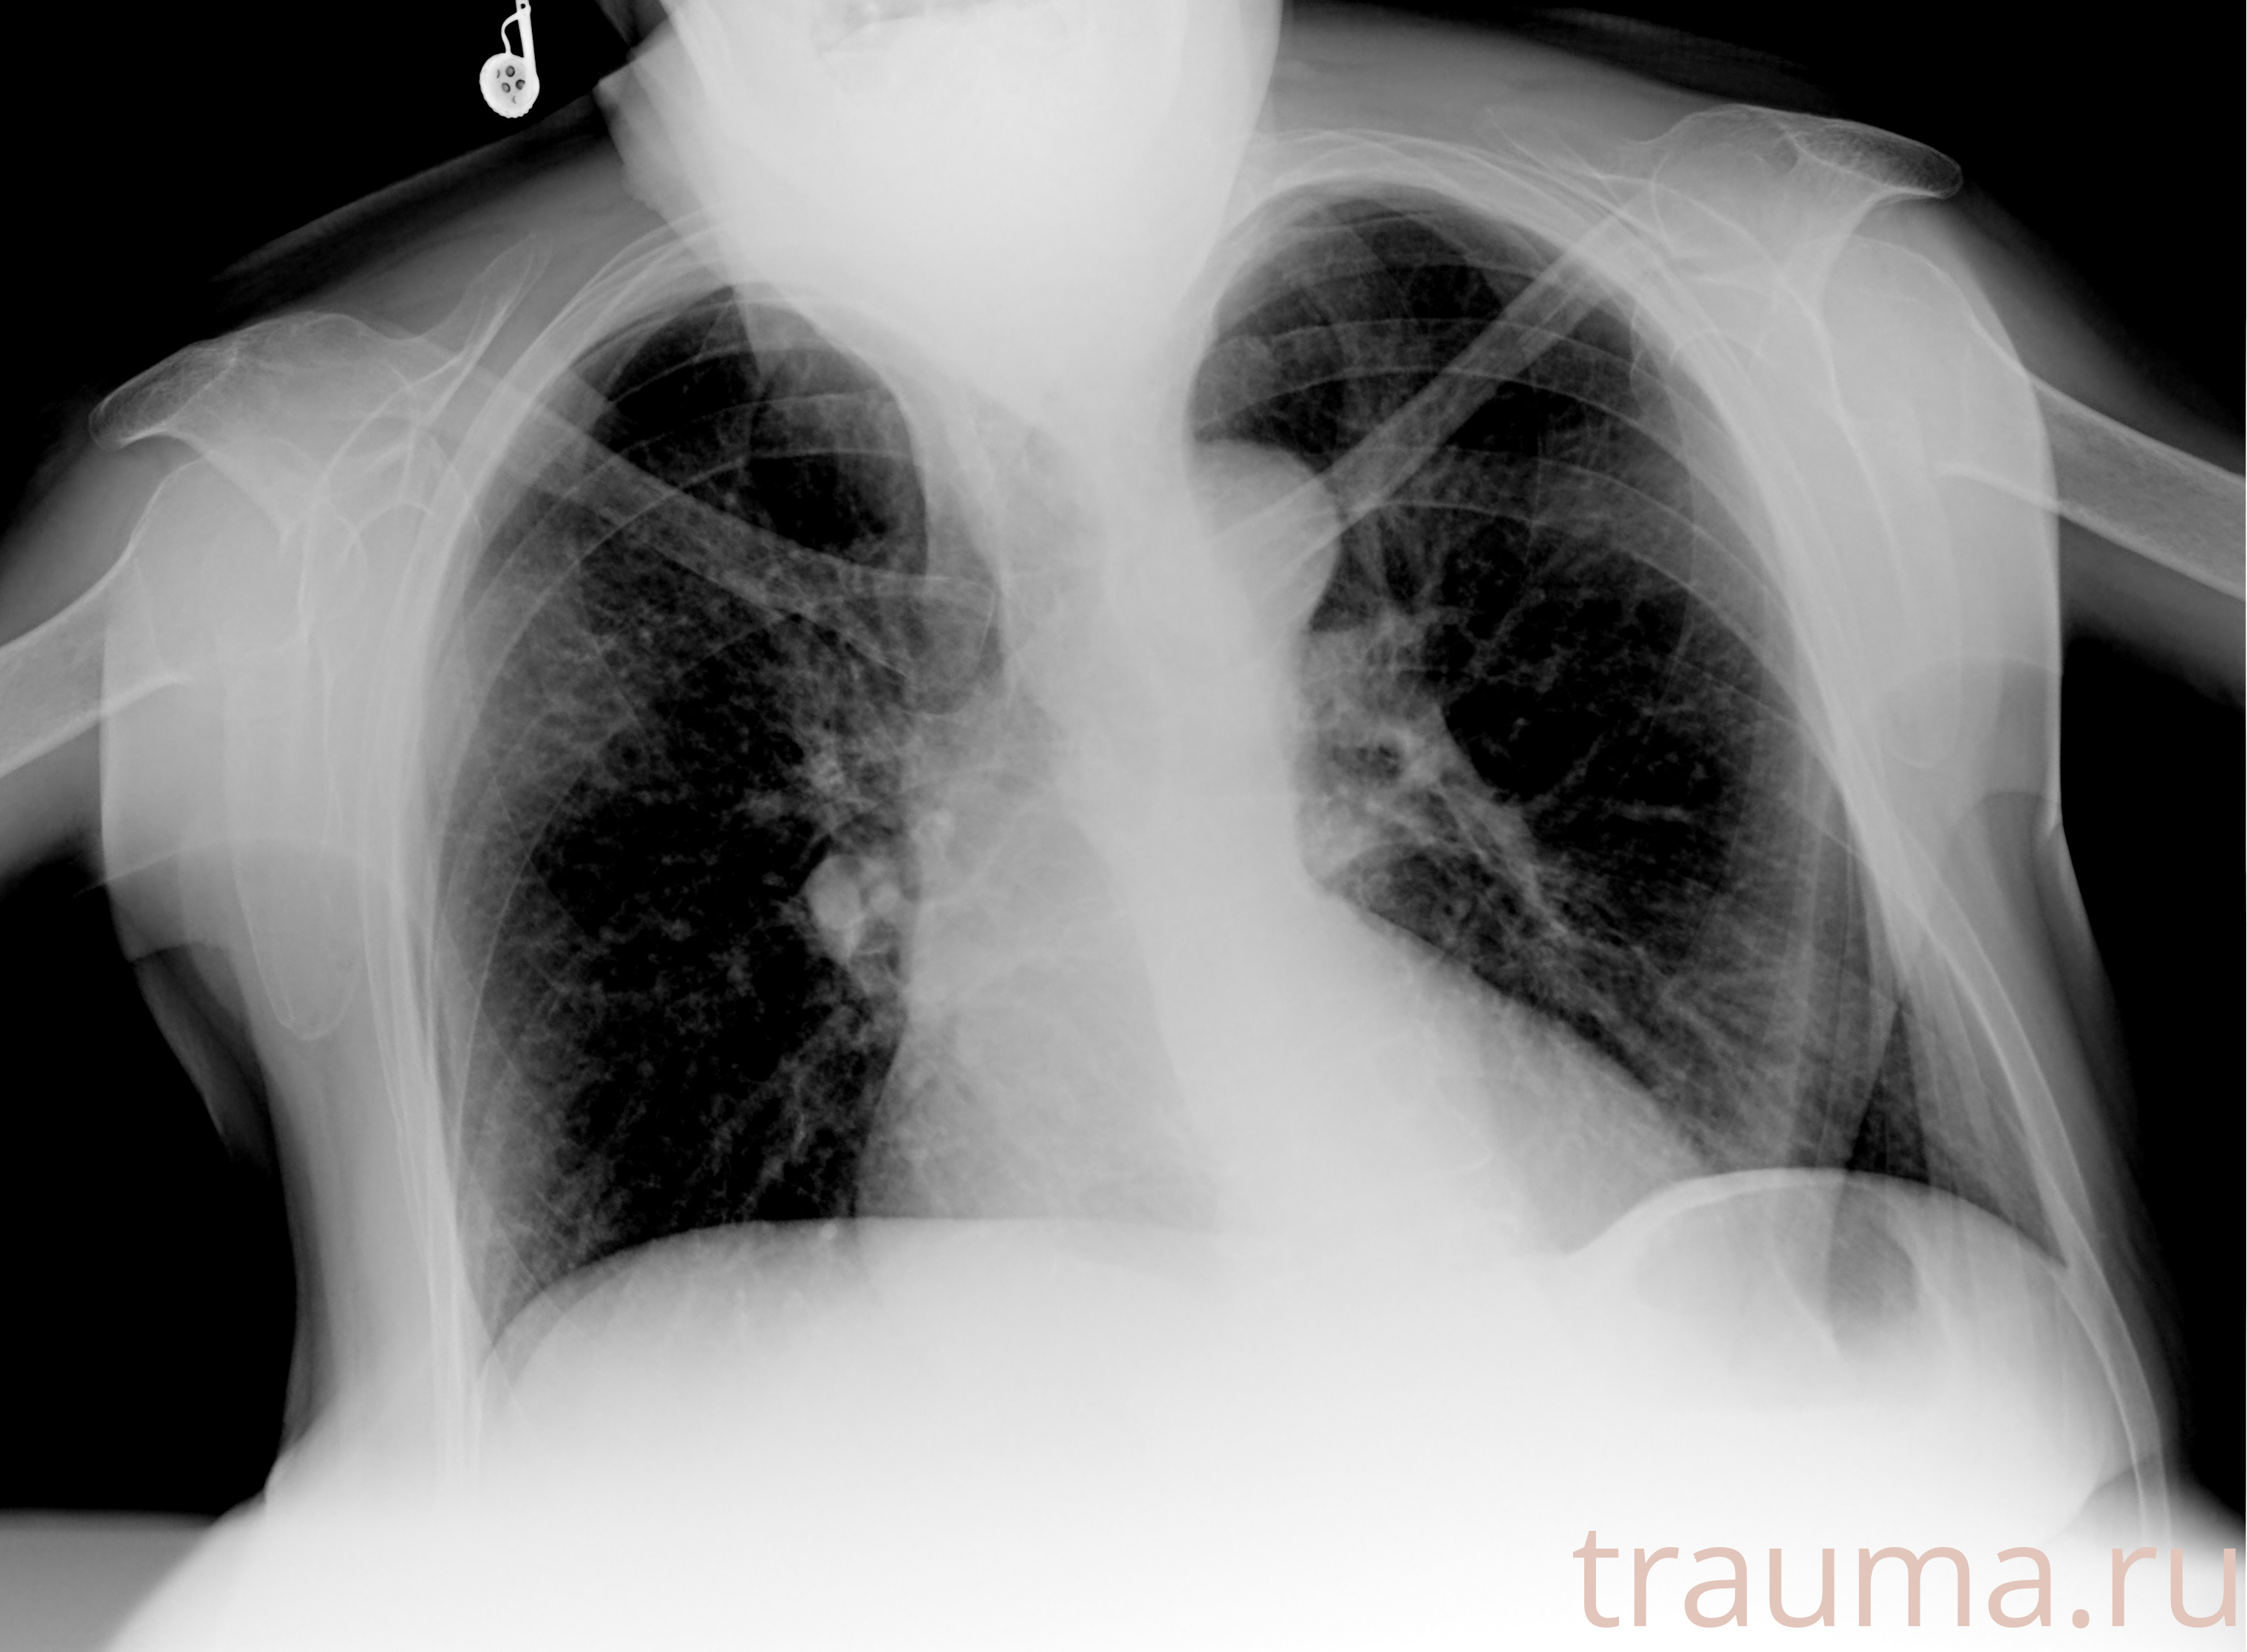

Рентгенограммы

Рентген на дому: по вашему адресу приезжает врач-рентгенолог, травматолог-ортопед с мобильным рентгеновским аппаратом, проводит диагностику травмы или заболевания, делает необходимые рентгенограммы, дает рекомендации по дальнейшему лечению. Получить качественные снимки в домашних условиях возможно благодаря уникальной методике, разработанной МосРентген Центром для института  Склифосовского

при переломе шейки бедра и пневмонии от компании МосРентген Центр - партнера Института имени Склифосовского